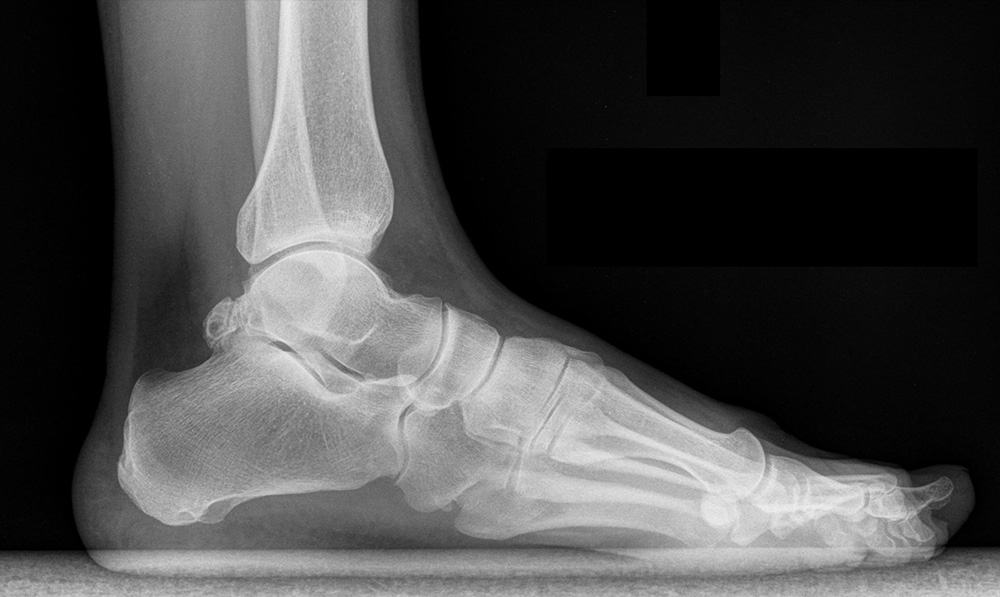

- Koniecznie badanie RTG;